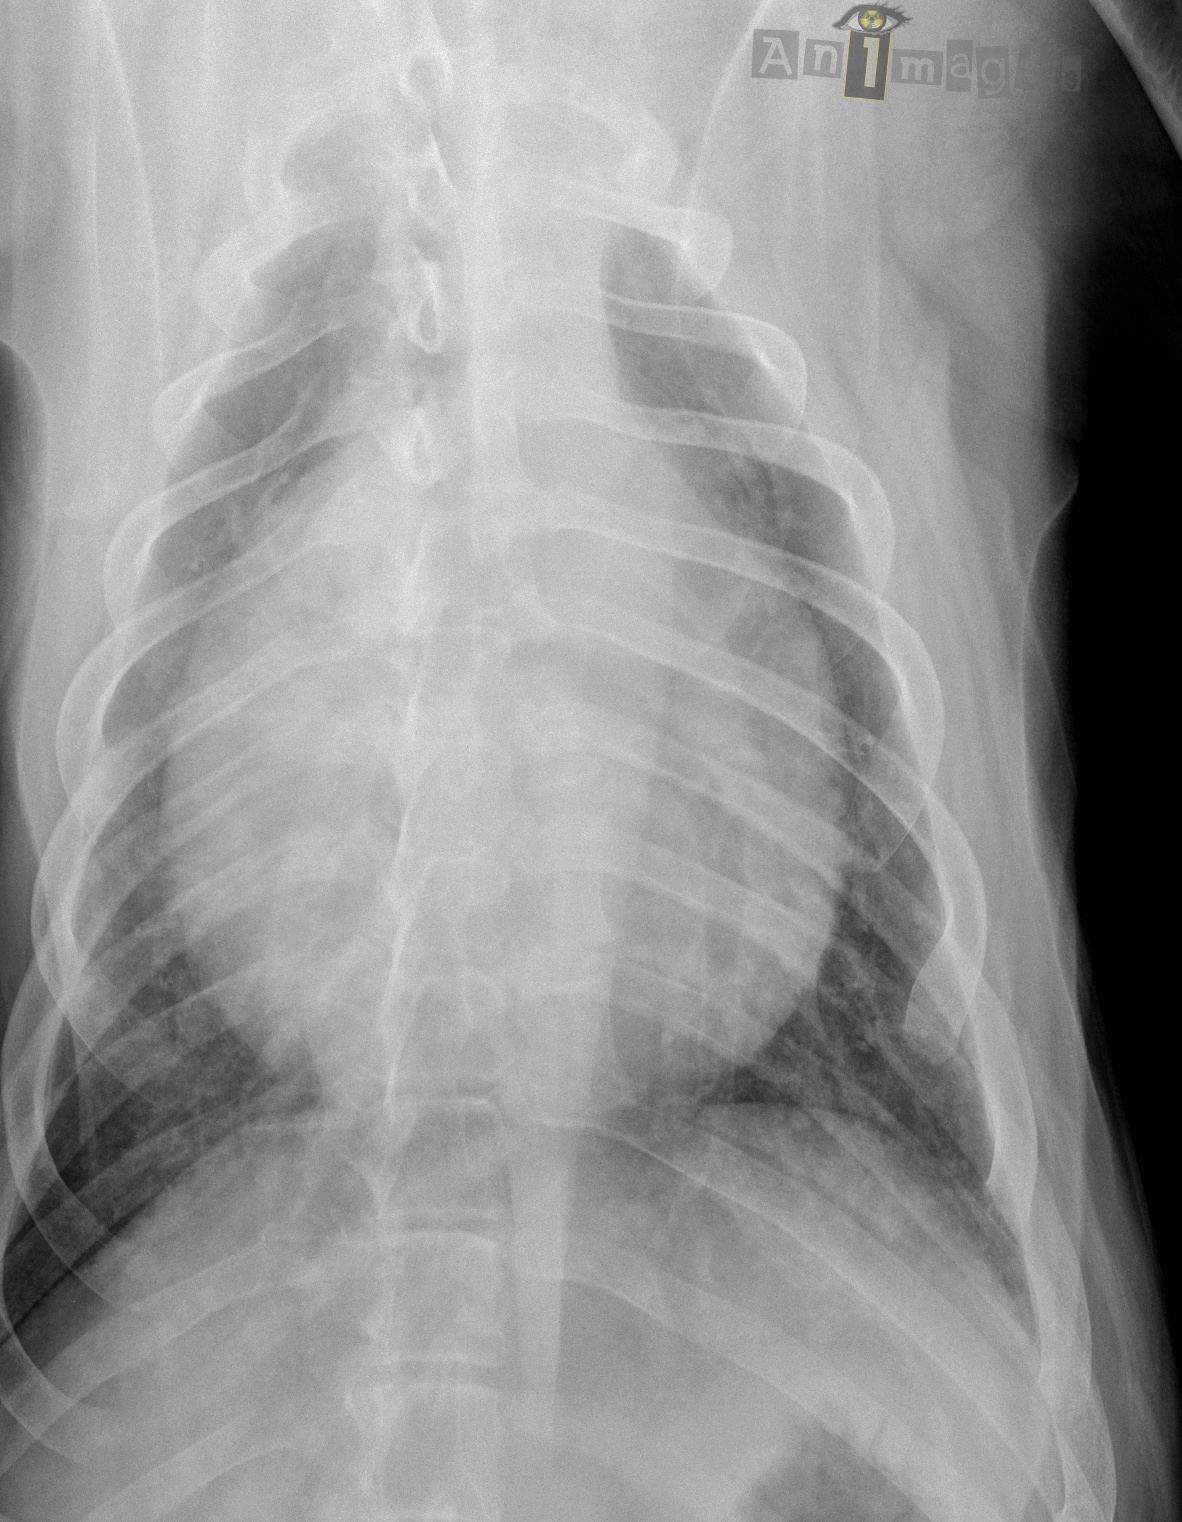

Dorsoventrale